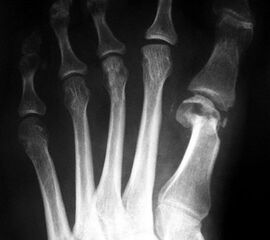

Die Röntgenaufnahmen (Abbildung 1) zeigen den Fuß einer 34 jährigen Patientin nach Exostosenabtragung. Der erhöhte intermetatarsale Winkel wurde durch eine alleinige Abtragung der Exostose nicht reduziert. Als weiterer Risikofaktor für ein Rezidiv liegt ein pathologischer Gelenkwinkel vor. Der intermetatarsale Winkel von 18 Grad kann durch eine basisnahe Osteotomie gut korrigiert werden. Da durch die gleichzeitige distale Korrektur des Gelenkflächenwinkels mithilfe einer Reverden-Green Osteotomie ein Längenverlust von ca. 2-4 mm einhergeht, bot sich als proximales Korrekturverfahren die basisnahe Open-wedge Osteotomie an, um bezüglich der Länge des Metatarsale I neutral zu bleiben (Abbildung 2). Die Kombination zweier verkürzender Verfahren (z.B. Lapidus und Reverden-Green) würden zu einem sehr kurzen ersten Strahl führen, mit dem Risiko einer Transfermetatarsalgie. Übersteigt die Verkürzung des Metatarsale I 2 mm, steigt das Risiko für die Entwicklung einer Transfermetatarsalgie deutlich an 8. Die durchgeführte Revision zeigt eine gute Stellung des 1. Strahls bei zentriert stehendem Gelenk.